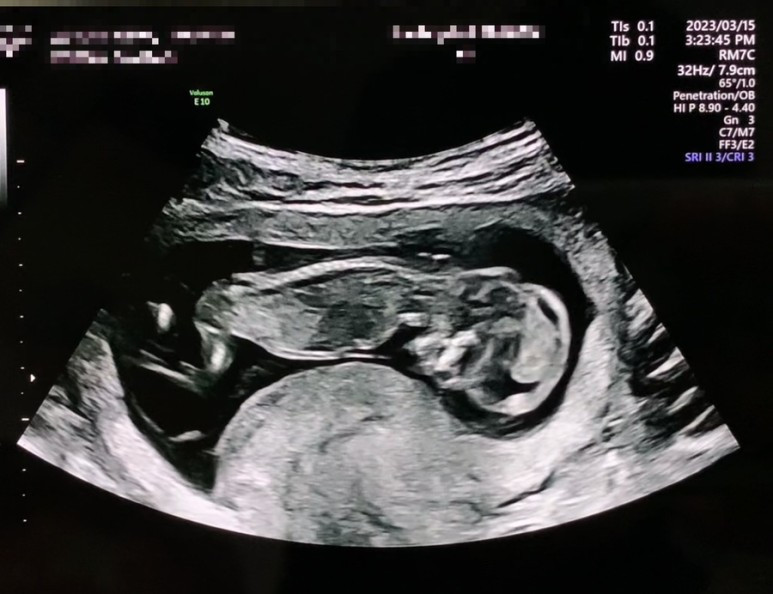

output_1584768733.jpg 왜인지 계속 엎드린 자세...

나부터라도, 현명하게 잘 헤쳐나가야지 다짐하면서 1차 정밀검사도 무사히 잘 마쳤고 이제 정말 인간의 형체를 띈 생명체를 보게 되었다. 신기... 예전에는 진짜 애벌레 같았는데 (남편은 자꾸 젤리곰이라고 정정하는데 애벌레가 어때서... 진짜 애벌레 같은데...) 그새 확실히 머리라고 할 수 있는 게 생겼고 손가락도 보였다. 9월에 봅시다요..!